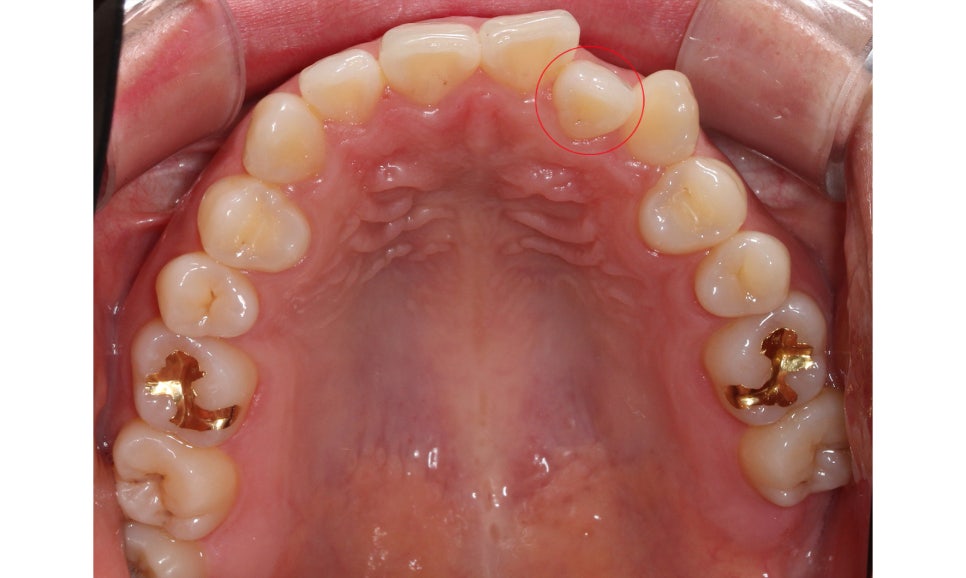

절단교합 교정 전 교합평면을 보면

상악과 하악의 교합 상태를 정확히

파악할 수 있습니다.

상악 교합면 사진입니다.

사진에서 우측 측절치가 설측으로

들어와 있어서 전치부

치열이 삐뚤거리는 모습인데요,

이러한 경우 들어와 있는 측절치를

원래 위치로 빼내기 위해서

주변 치아들을 이동시켜 공간을 만들어 주어야 합니다.

교정 초기에 이 부분에 open coil spring이

(공간확보 용)결찰될 수 있습니다.